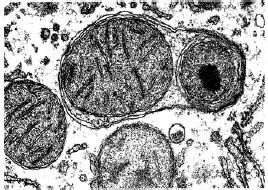

由於自噬體屬於亞細胞結構,普通光鏡下看不到,因此,直接觀察自噬體需在透射電鏡下。Phagophore的特徵為:新月狀或杯狀,雙層或多層膜,有包繞胞漿成分的趨勢。自噬體(AV1)的特徵為:雙層或多層膜的液泡狀結構,內含胞漿成分,如線粒體、內質網、核糖體等。自噬溶酶體(AV2)的特徵為:單層膜,胞漿成分已降解。(autophagicvacuole,AV)。